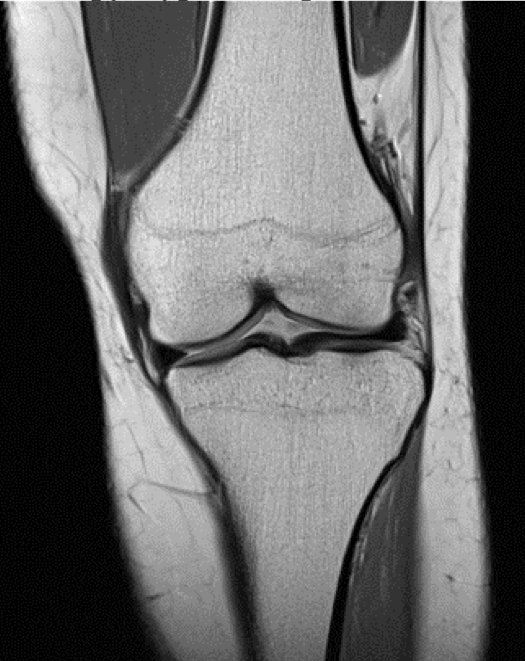

Выберите верный вариант о структуре, изображённой на МРТ снимке.